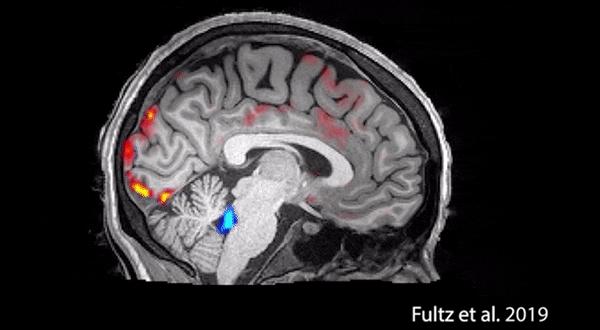

睡觉时,血液会周期性地大量流出大脑。每当血液大量流出,脑脊液就趁机发动一波攻击。脑脊液进入之后会清除毒素,比如导致阿尔茨海默病的β淀粉样蛋白。而这样的清洗,只有在睡着后才能做到,让人一觉醒来,拥有一个清爽的大脑。下图是波士顿大学的科学家们,史无前例地拍下了清洗过程:

红色是血液,蓝色是脑脊液。从前没有发现的是,血液会周期性地大量流出大脑。每当血液大量流出,脑脊液就趁机发动一波攻击。脑脊液进入之后会清除毒素,比如导致阿尔茨海默病的β淀粉样蛋白。